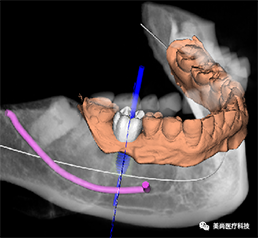

B.绘制下颌神经管

E.软件上修复体设计

F.选择牙位添加种植体

G.选择合适的导环全程或者定位完成植体设计